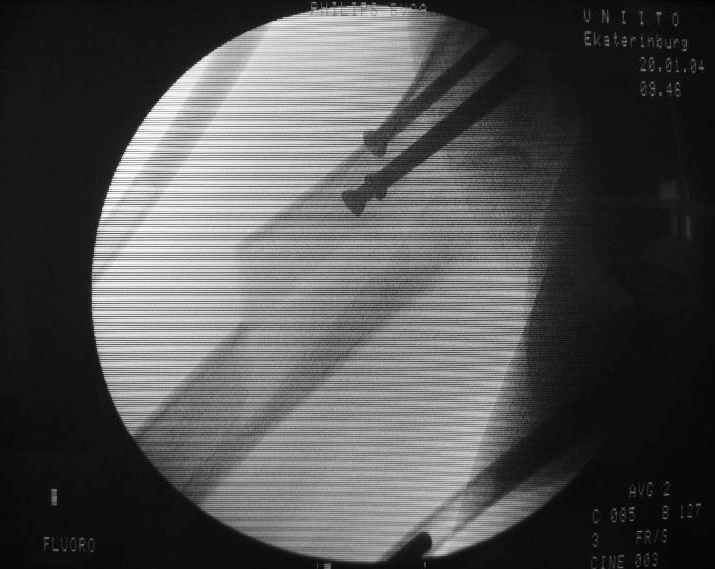

Вчера оперировали - винты удалены через 1 прокол. Затем выполнили закрытый интрамедуллярный остеосинтез без расверливания бесканальным гвоздем 13 мм (реконструкционного для нее не нашлось). Гвоздь заперт статически - в проксимальный отломок 3 винта 6 мм, в дистальный - 1.

Учитывая варус сросшейся шейки, постарался вальгизировать проксимальный отломок, насколько гвоздь позволил. Результат в приложении. Картина перелома видна лучше, чем на начальных снимках.

Интересно, что линия перелома не выходила на отверстия от винтов, а была кзади. Комментарии?

The screws were removed through a stab wound. Then a closed insertion of an unreamed solid nail 13 mm was performed and the nail statically locked - 3 screws 6 mm in the proximal fragment and 1 in the distal.

Considering varus of the healed neck i tried to get some valgus to the proximal fragment as the nail allowed. The result attached. The fracture pattern can be seen better than in the initial films.

Any comments?